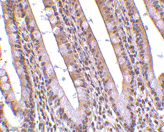

Below: PHAP I might be differently spliced isoforms of PHAP. Below: Immunohistochemistry of PHAP in human small intestine tissue with PHAP antibody at 10 µg/ml.

Application : PHAP antibody can be used for detection of PHAP I and PHAP III by Western blot at 0.5 to 2 µg/ml.At approximately 35 kDa and 32 kDa a band can be detected.